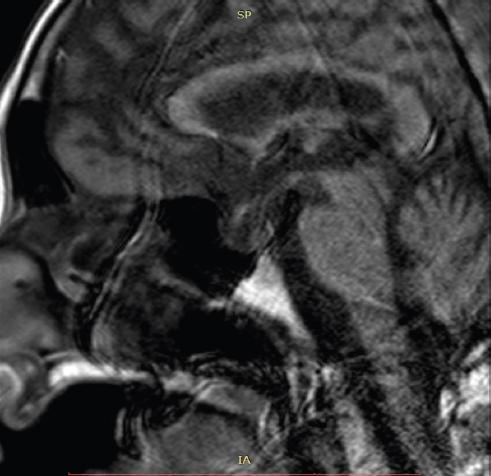

Mujer de 68 años con antecedente de hemorragia posparto a los 33 años de edad, sin secuelas clínicas tras dicho evento (agalactia ni amenorrea). Sin antecedentes familiares de insulinoma. Se le diagnosticó trastorno depresivo mayor a los 38 años, en manejo con fluoxetina. En la entrevista negó otras enfermedades crónicas degenerativas. Su padecimiento actual inició el día 12 de abril de 2019, cuando acudió a un hospital privado por presentar astenia, adinamia, diaforesis, debilidad, confusión y somnolencia; el manejo médico inicial incluyó control de deshidratación grave y de hipoglucemia mediante soluciones glucosadas parenterales, siendo egresada al tercer día por aparente mejoría general. Veinticinco días después del inicio de este cuadro presentó de nuevo la misma sintomatología, pero en esta ocasión fue llevada al servicio de urgencias de nuestro hospital. A su ingreso, la paciente presentaba un cuadro clínico caracterizado por hipoglucemia grave con debilidad, mareo, confusión y somnolencia. Los exámenes de laboratorio mostraron una concentración de glucosa sérica de 30 mg/dl y una anemia normo-normo (volumen corpuscular medio [VCM] de 87 fl y hemoglobina corpuscular media [HCM] 31 pg) asociada a hemoglobina de 9.0 g/dl, hematocrito del 24.4% y leucocitopenia de 3.9 × 10 9/l. Se le administró una carga de solución glucosada al 50% por vía parenteral que condicionó un alivio casi inmediato de los síntomas, lo que se conoce como la tríada de Whipple (baja concentración de glucosa en sangre, síntomas de hipoglucemia y mejoría una vez normalizada la glucemia). Fue ingresada al servicio de medicina interna para continuar con el protocolo de estudio de la hipoglucemia. En la tabla 1 se detallan los estudios de laboratorio al ingreso de la paciente en el servicio de urgencias, en los que son evidentes la hipoglucemia grave y la anemia. Tras su ingreso al servicio de medicina interna, la exploración física reveló despigmentación de la piel principalmente de las aréolas mamarias, involución mamaria y pérdida del vello axilar y púbico; no se encontraron estigmas de hepatopatía crónica. Los signos vitales eran normales. La presencia de insuficiencia renal, hepatopatía crónica e hipoglucemia secundaria a medicamentos u otras sustancias, tales como insulina, sulfonilureas, glinidas o alcohol, se descartó por la información y los antecedentes obtenidos en la historia clínica. Se indagó acerca de algún proceso séptico o inanición que explicaran la hipoglucemia, sin éxito. Para la evaluación de hipocortisolismo e hiperinsulinismo como causa de la hipoglucemia se determinaron el cortisol sérico y la insulina endógena; con los resultados obtenidos se pudo determinar la presencia de hipocortisolismo y valores disminuidos de insulina endógena, al contrario de lo que se podría esperar en una hiperinsulinemia. En la tabla 2 se muestran los resultados de los estudios de laboratorio realizados durante la estancia de la paciente en el servicio de medicina interna, en los que son evidentes el hipopituitarismo y el hipotiroidismo. En la tomografía computarizada de abdomen no se evidenciaron masas tumorales en el páncreas ni en la cavidad abdominal, y por lo tanto se descartó la hipótesis de un insulinoma como causante de la hipoglucemia. En virtud de los valores bajos de cortisol sérico se realizó una resonancia magnética de cráneo en busca de alteraciones anatómicas, y el resultado fue la presencia de una silla turca vacía, por lo que con el antecedente de hemorragia posparto, el panhipopituitarismo y el estudio de imagen se consideró que se trataba de un síndrome de Sheehan. En la figura 1 se muestra el resultado de la resonancia magnética de cráneo que mostró la silla turca vacía. Una vez con el diagnóstico, se inició tratamiento con reemplazo hormonal. Se administró prednisona a dosis de 5 mg/24 h por vía oral. Se eligió este fármaco porque es el disponible en nuestra institución. Las guías recomiendan el uso de hidrocortisona por vía oral como primera opción de tratamiento hormonal sustitutivo12-14, pero en México no contamos con este preparado. Se administró levotiroxina ajustada de acuerdo con el peso de la paciente a dosis de 1.6 mg/kg de peso corporal cada 24 horas (dosis final de 100 mg al día) para controlar los síntomas hipotiroideos y prevenir complicaciones como el coma mixedematoso. La mejoraría del cuadro clínico fue evidente a los 14 días de iniciado el tratamiento.

La falla de la glándula pituitaria ocurre bajo varias condiciones: enfermedades hipotalámicas como craneofaringiomas, metastasis de tumores primarios de pulmón o mama, secundaria a radiación del sistema nervioso central, infecciones como meningitis tuberculosa y traumáticas, y enfermedades hipofisiarias como adenomas o quiste de hipófisis, cirugía hipofisaria, radiación hipofisaria, hemocromatosis, infección o absceso hipofisario, y causas vasculares como apoplejía y síndrome de Sheehan. El hipopituitarismo relacionado con el síndrome de Sheehan es poco frecuente. El síndrome de Sheehan es más común en los países en vías de desarrollo15. Su diagnóstico se fundamenta en el antecedente de hemorragia posparto, falla en la lactancia, deficiencia de hormonas hipofisarias y presencia de una imagen radiológica de silla turca vacía en un estudio de resonancia magnética de cráneo16. Nuestra paciente cumplía todos los criterios, pero su presentación atípica ocurrió 35 años después del evento de hemorragia posparto y sin falla en la lactancia ni amenorrea. En los últimos años se han publicado varias series de casos sobre la presentación clínica tardía del síndrome de Sheehan17-22.